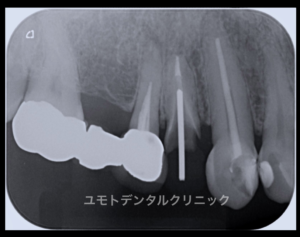

「補綴を除去した際にパーフォレーション部分を確認した」

歯の保存のためのパーフォレーションリペアを含めた根管治療のご紹介をいただきました。

開始直後の状態になります。

低倍率でも髄床底にあるパーフォレーション部分を確認いたしました。

しかしこのケースにおいてはパーフォレーション部周囲に複数のクラックを生じている状態でした。

確認後メチレンブルー染色にてこのクラックが染まることを確認いたしました。